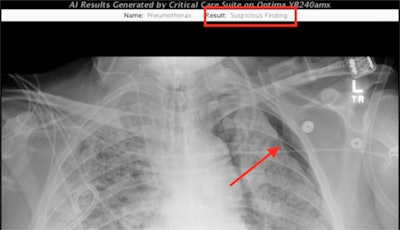

The applications include an AI algorithm for pneumothorax screening that was co-developed by GE and UCSF researchers Dr. John Mongan, PhD, and Dr. Andrew Taylor, PhD. The pneumothorax algorithm received U.S. Food and Drug Administration 510(k) clearance in 2019.